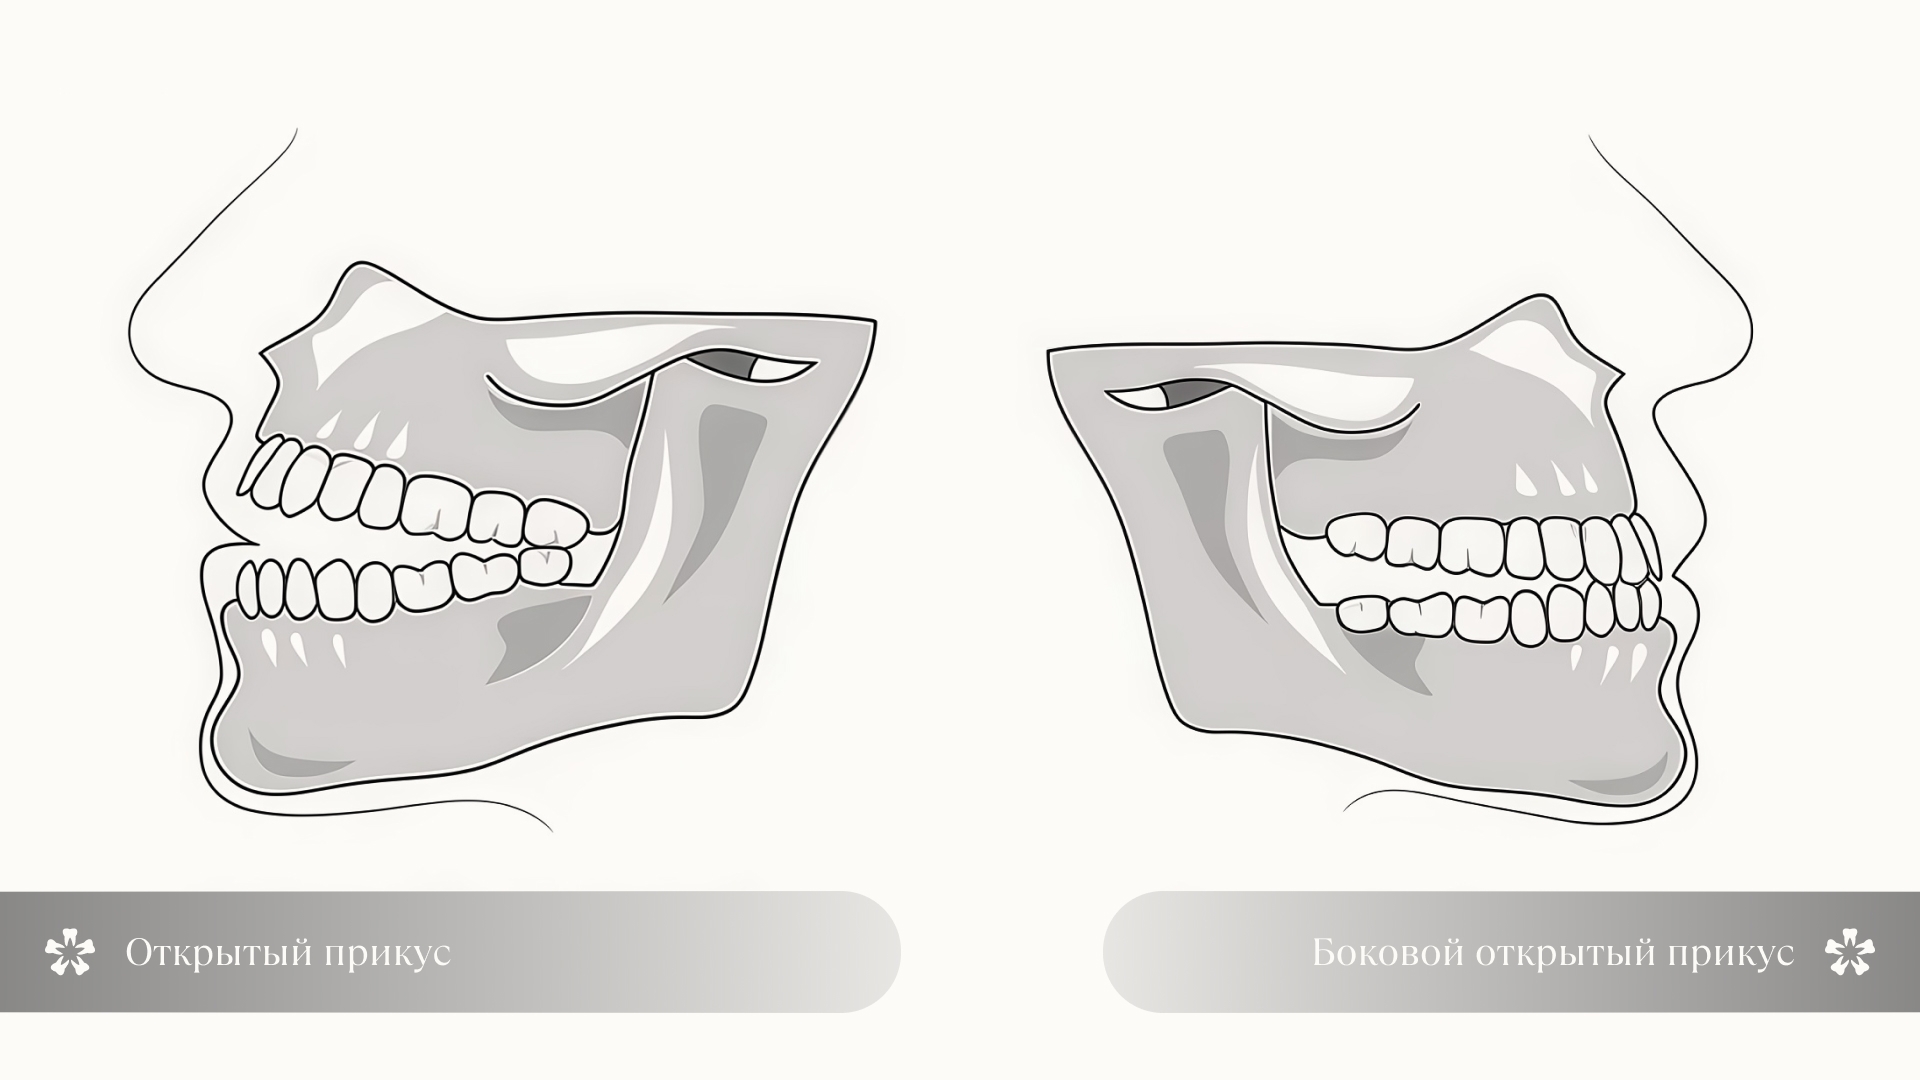

Открытый прикус — это форма неправильной окклюзии, при которой у ребенка не смыкаются зубы при закрытом рте. Между рядами сохраняется вертикальная щель, чаще всего в переднем отделе, из-за чего нарушается нормальное жевание, речь и положение губ в покое.

- Фронтальный (передний). Самый распространенный тип. При смыкании зубных рядов между передними зубами (резцами и клыками) остается вертикальная щель. Такой прикус легко заметить визуально: зубы не смыкаются, а рот остается чуть приоткрытым даже в покое.

- Боковой. Редкий тип, при котором щель формируется не спереди, а в области боковых зубов: премоляров и моляров. Может быть односторонним (с одной стороны челюсти) или двусторонним. Часто связан с макроглоссией (увеличенным языком) или деформацией боковых отделов челюсти.